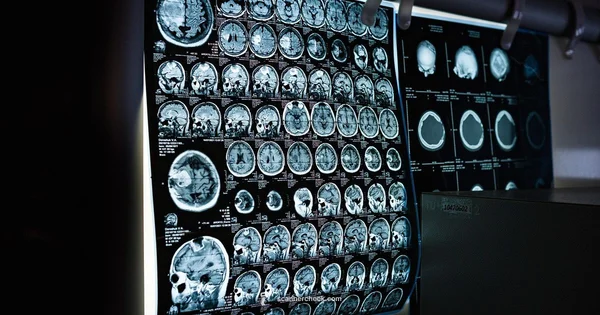

Images are interpreted by a radiologist who writes a report describing anatomy, any abnormalities, and suggested next steps. The report is sent to your clinician who will discuss findings with you and decide whether additional imaging, follow up visits, or treatment changes are needed. In some cases, MRI findings are routine and reassure; in others they prompt urgent interventions or continued monitoring. The results integrate with your symptoms, history, and other tests to form a comprehensive care plan.